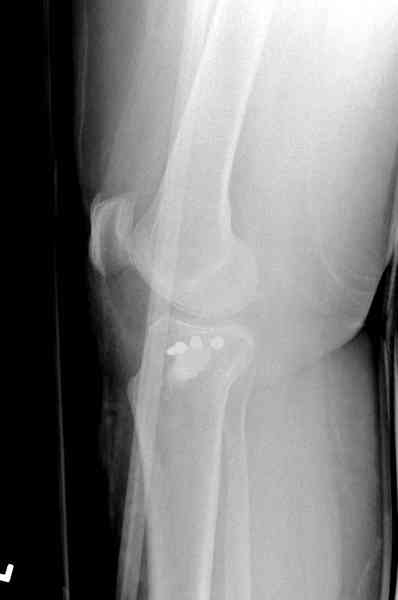

Здравствуйте, уважаемые коллеги!Подскажите, пожалуйста, какой выбрать доступ и способ фиксации при импрессионном переломе заднего отдела наружного мыщелка большеберцовой кости. Женщина 40 лет, травму получила 02.01.2008, катаясь на горных лыжах.Есть ли здесь необходимость использовать задний доступ, или можно справиться через наружный? Есть ли шансы сделать закрыто - под ЭОП через медиальное "окошко" поднять забойником суставную поврехность? Какой лучше использовать фиксатор?Спасибо.

In this situation, where the fragment is posterolateral, one needs a posterior approach, either as described by Timothy Bhatacharya et al in 2005 in JOT, which involves taking down the medial head of the gastrocnemius, or the Lobenhoffer paper which involves a transfibular approach.

would anyone consider an anterolateral approach with a sagital osteotomy just lateral to midline?

this would give access to the impacted posterior region. then "backgraft", and fix the osteotomy

fragment with a standard anterolateral plate. thanks.